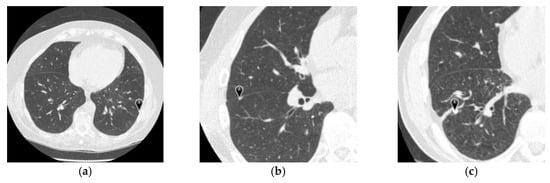

3.1. Four-Type Nodule Classification